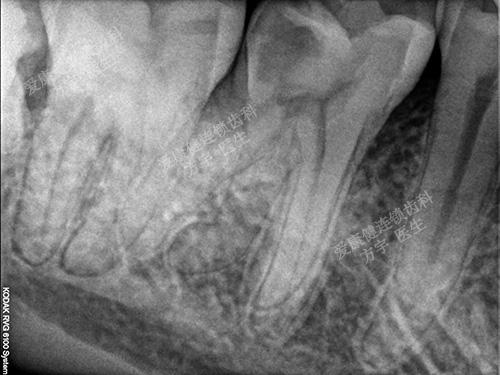

术后